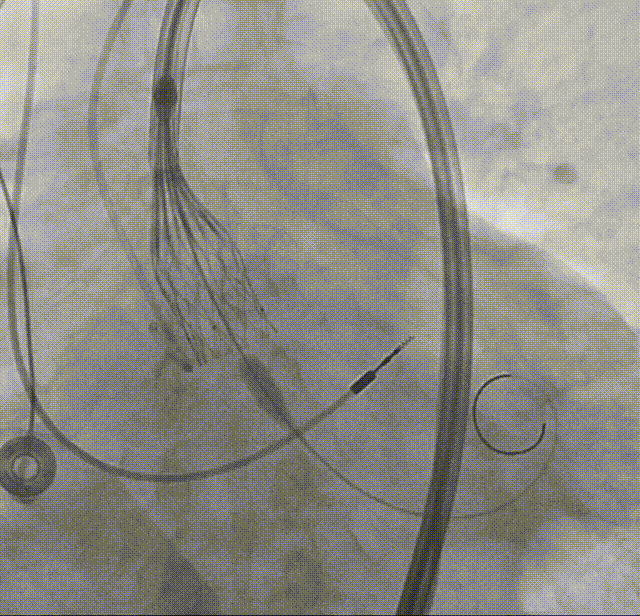

输送系统顺滑过弓

瓣下1mm初始定位

瓣膜释放至全展开位

全展开位评估:锚定区呈直筒状,瓣架中段微收腰,瓣膜形态佳